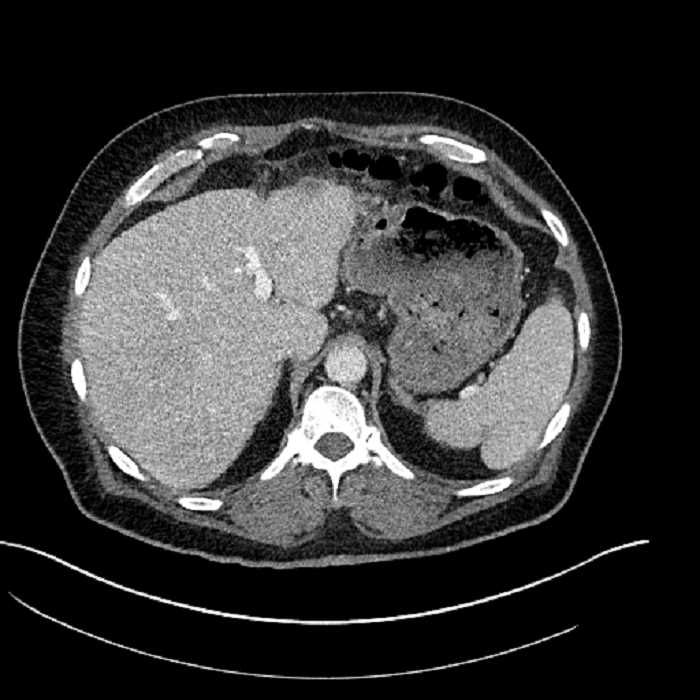

Age: 63

Sex: Male

Indication: Abdominal pain

• Large fluid density structure in hepatic segments 7 and 8 measuring 10 x 7 x 7 cm with internal septation and circumferential ill-defined low density compatible with edema

• Peripherally enhancing subcapsular collections along the anterior margin of the left hepatic lobe measuring 3 x 1 cm and 2 x 1 cm

• Clearly marginated fluid density structure in segment 7 and several other scattered tiny hypodensities, which likely represent cysts

• Hepatic abscess

Acute sigmoid diverticulitis complicated by a small contained perforation and a large abscess in the right hepatic lobe. Additional small subcapsular abscesses along the anterior margin of the left hepatic lobe.

• The classic CT imaging appearance is a double target sign with internal low density surrounded by an internal enhancing rim (capsule) and a low density external rim (edema)

Hepatic abscess showing the double target sign with low density internally surrounded by a thin inner enhancing rim (red arrow) and ill-defined outer low density rim (yellow arrow). Blue arrow indicates an internal septation. Red arrows: additional smaller subcapsular abscesses. Red arrow: focal contained perforation associated with diverticulitis.